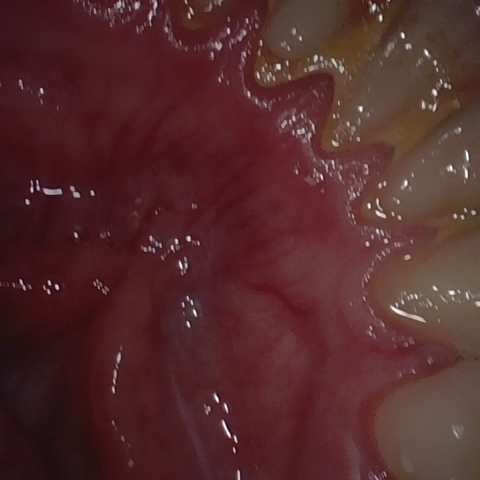

NHD39455

Overview

Annotated as "Good"